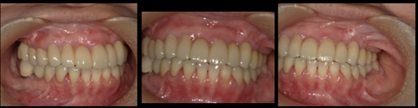

インプラント6本埋入+FGG(60代女性)

治療前

治療後

施術名 | インプラント6本埋入+FGG |

主訴 | 噛めない |

施術の副作用(リスク) | 脱落感染 |

施術の価格 | 施術の費用 1本GBR5万~10万(税抜き)+インプラント埋入補綴まで35万(税抜き) |

コメント | 下の前歯は再生療法ブリッジを行い歯を保存しました |